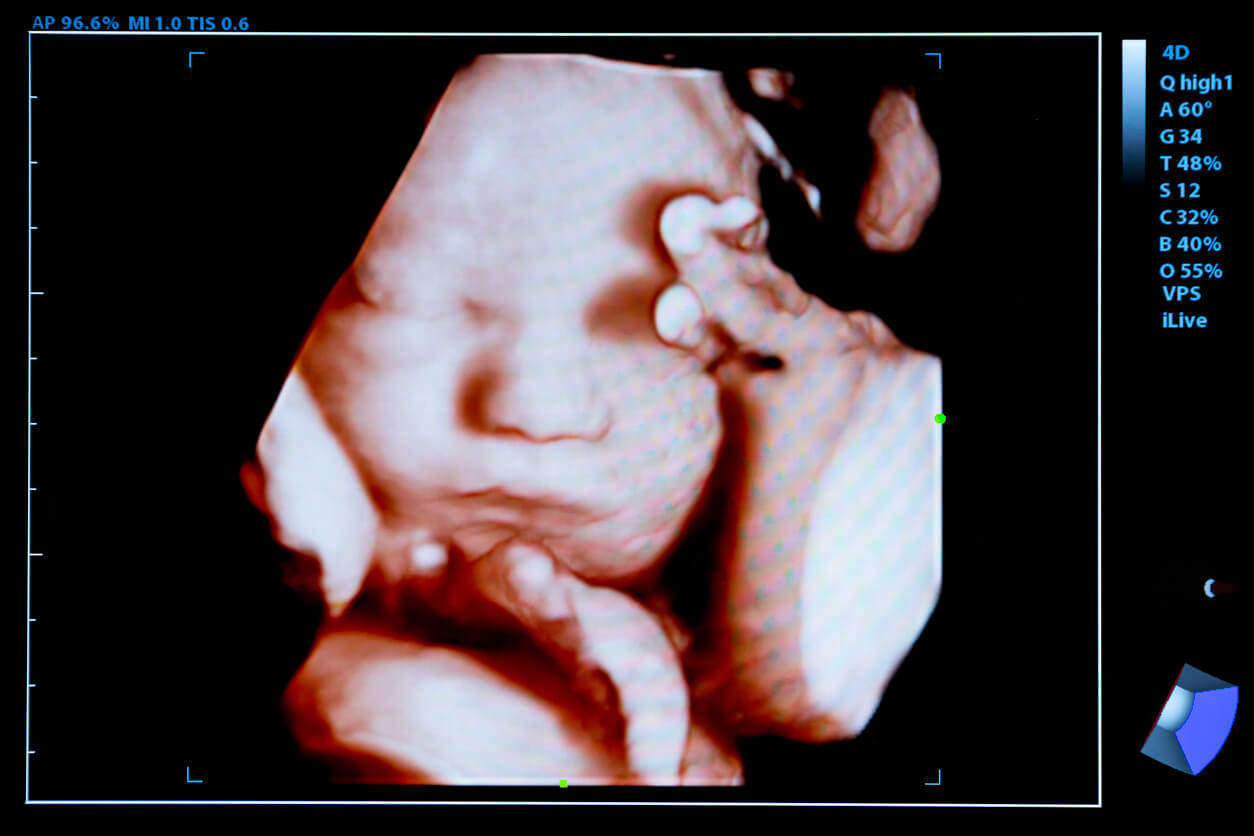

La coloración del cabello del bebé depende de la genética, es decir, del ADN que se hereda de los padres. Los folículos empiezan con su proceso de desarrollo alrededor de la semana 14. Ya para la semana 15 se puede visualizar un patrón de cuero cabelludo característico.

Segundo trimestre

En el transcurso del segundo trimestre, el cuerpo del bebé se encuentra recubierto por lanugo, que es un cabello suave que se presenta en la vida intrauterina para mantenerlo caliente. Más adelante, este cabello sedoso se desprenderá de manera espontánea, pero puede persistir algún remanente al momento del nacimiento.